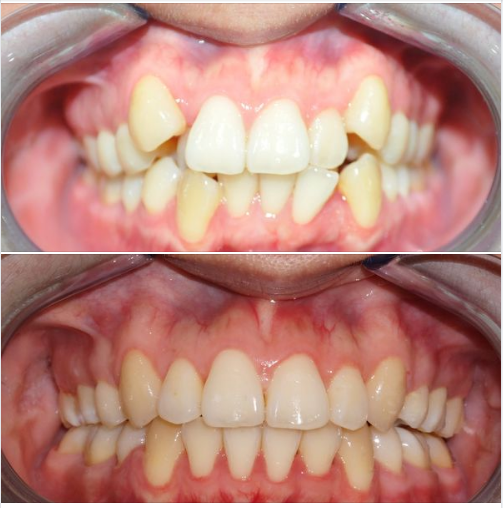

P/s: Hình ảnh một ca niềng răng mắc cài trong 2.5 năm.